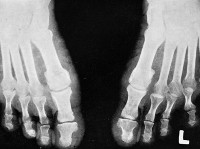

Стопа деформируется, движения в суставах ограничиваются. Нарушается корешковая чувствительность, исчезают ахилловы рефлексы. Температурная и болевая чувствительность сохранены, тонус мышц снижен. Таким образом, формируется характерная для псевдосирингомиелитической акропатии триада симптомов: вялое акроизъязвление, остеопороз и деструкция костей стоп, полинейропатия с частичной или полной потерей температурной чувствительности.

Клинический диагноз выставляет дерматолог на основании анамнеза, характерных симптомов псевдосирингомиелитической акропатии, результатов морфологических исследований и данных рентгеновского обследования, при проведении которого обнаруживаются явления прогрессирующего артрита, «наползание» костей друг на друга, вывихи, переломы и участки деструкции костей стоп. Гистологически отмечается развитие фиброза в симпатических узлах поясничного отдела позвоночника и нарушения в задних отделах спинного мозга.